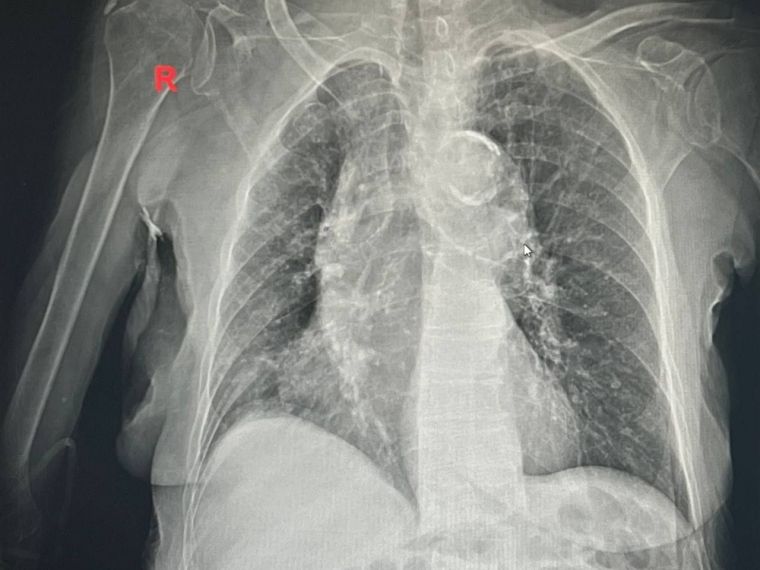

«Пару недель назад в приемное отделение больницы поступила пациентка в возрасте 100 лет с обострением хронического бронхита легких. Женщина болела в течение пяти дней и в один момент почувствовала, что ей стало хуже. После этого муж правнучки вызвал скорую и привез бабушку в больницу, с температурой тела 40 градусов», — рассказали в ведомстве.

В стационаре медики делали все, чтобы помочь пациентке в течение четырех дней, после чего в удовлетворительном состоянии она была выписана домой.

Пациентке были даны все необходимые рекомендации специалистов по физическим нагрузкам, диете, контролю давления и другим факторам для дальнейшего амбулаторного лечения.